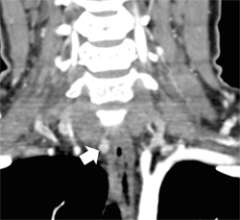

Figure 1b. Parathyroid 4D-CT showing a parathyroid adenoma in an abnormal position within the carotid sheath, missed during a prior surgery. CA= Carotid artery.